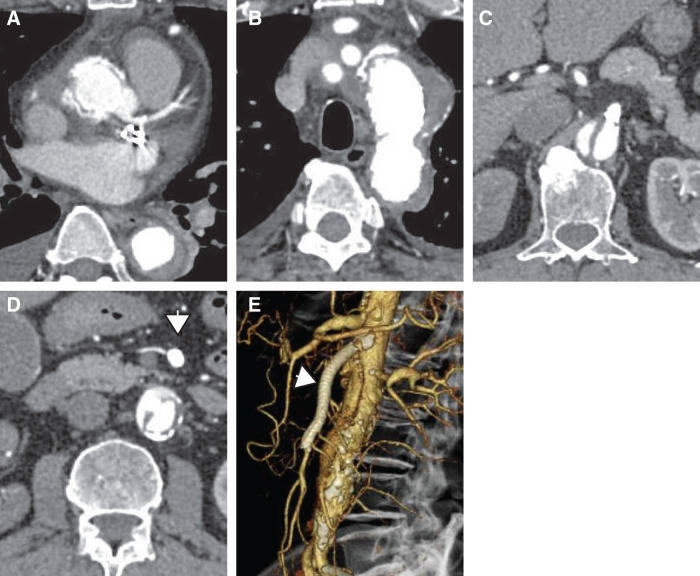

Case presentation: A 71-year-old male presented with acute chest pain and was diagnosed with Stanford Type A AAD extending to the abdominal aorta, with superior mesenteric artery (SMA) dissection leading to intestinal ischemia. To restore intestinal perfusion, emergency endovascular SMA stenting was performed as the initial intervention, followed by ascending aorta and total arch replacement using the frozen elephant trunk technique 12 hours later. The patient recovered without complications and was discharged ambulatory on postoperative day 20.

Conclusions: This case highlights the efficacy of a staged approach prioritizing mesenteric revascularization before central aortic repair in AAD complicated by visceral malperfusion. By first addressing end-organ ischemia, we potentially mitigated the risk of irreversible bowel necrosis while enabling subsequent central aortic repair. Our experience adds to the growing body of evidence supporting individualized, pathophysiology-guided treatment strategies for this challenging clinical scenario.